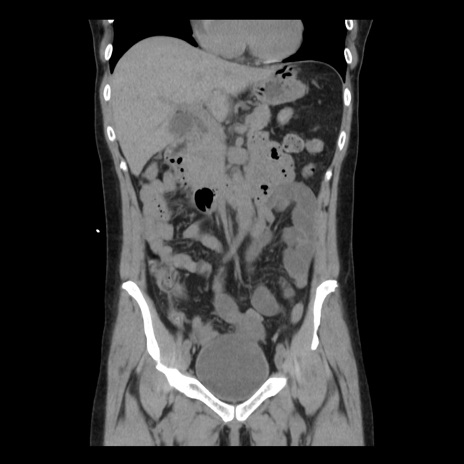

症例10(冠状断像)

【症例】 50歳代女性

【主訴】 腹痛

【現病歴】前日生レバーを食べた。今朝に排便あり。 昼前に突然発症の腹痛を生じ、当院救急外来を受診した。

【既往歴】 子宮筋腫にてで子宮全摘後

【身体所見】 意識清明、腹部:平坦、軟、下腹部やや左を中心に圧痛・反跳痛あり、筋性防御あり

【データ】WBC 7800、CRP 0.07